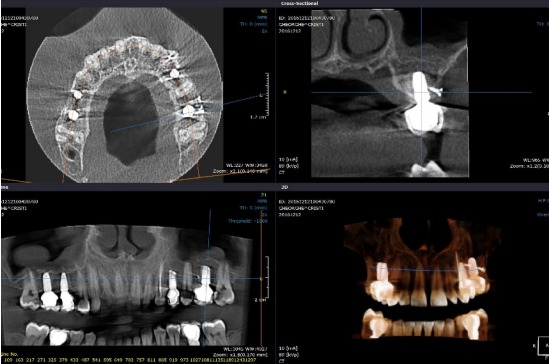

Unul dintre cei mai importanți pași în clinica noastră, sunt analizele. Detaliile și complexitatea acestor analize, le vei găsi în Ghidul Implantului Dentar.

Fără analizele corecte și fără informațiile exacte, medicul dentist poate fi asemănat cu un căpitan de vapor care navighează fără busolă, iar tratamentul ar fi unul imprecis.

Toate aceste analize se realizează în clinică. Dispunem de toată aparatura modernă necesară.

Pe baza informațiilor, putem realiza planul de tratament medical, putem evalua costurile și bugetul. Abia apoi putem face o estimare de timp.